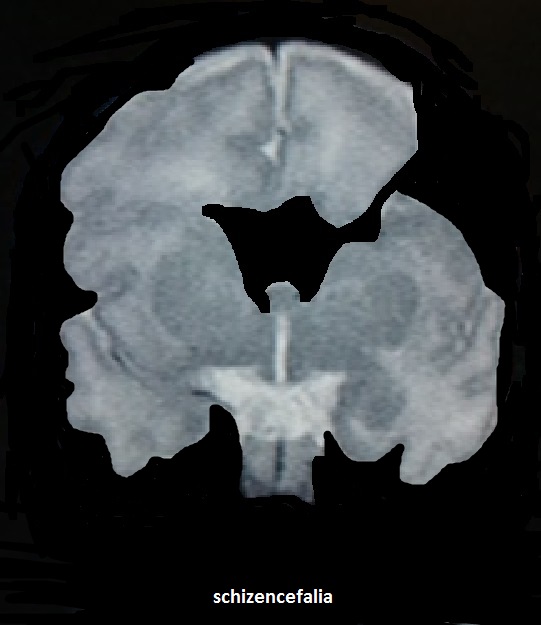

La schizencefalia è conseguenza della precoce interruzione dello sviluppo degli emisferi cerebrali con formazione di una fessura (schisi) che mette in comunicazione i ventricoli cerebrali laterali con gli spazi liquorali periferici.Tali comunicazioni possono essere a "labbra aperte" o a "labbra chiuse", unilaterali o bilaterali. La definizione a labbra aperte o chiuse si riferisce all'apposizione o meno della corteccia cerebrale adiacente alla fessura.

Tale caratteristica delinea due forme di Schizencefalia:

Schizencefalia tipo I caratterizzata da comunicazioni strette e labbra fuse in alcuni settori;

Schizencefalia tipo II caratterizzata da comunicazioni più ampie, labbra aperte e formazione di una cavità riempita da abbondante liquido cerebrospinale.

Il secondo tipo è l'unico riportato in letteratura in diagnosi prenatale ed è caratterizzato da una schisi che si estende dalla superficie corticale ai ventricoli laterali dilatati. La sede più comune è la scissura silviana. E' frequente (50-75% dei casi) l'associazione con la Displasia setto-ottica. Inoltre vi è correlazione tra topografia lobare delle fessure e presenza o meno del setto pellucido: tutti i casi con setto pellucido assente presentano fessure nel lobo frontale, mentre tutti i casi con setto pellucido presente hanno fessure a livello dei lobi parietale, temporale e occipitale.